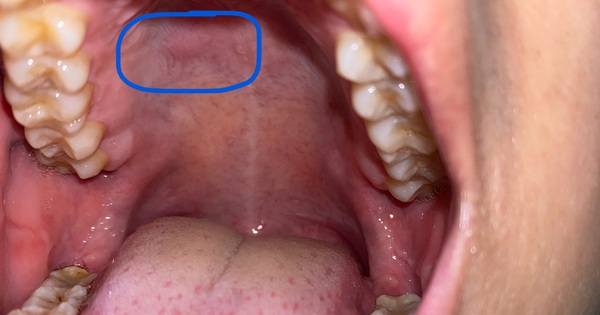

4. Thay đổi màu sắc của niêm mạc miệng

Niêm mạc miệng bình thường có màu hồng, nếu chuyển sang màu trắng, nâu hoặc đen nghĩa là tế bào biểu bì niêm mạc đã bị biến đổi. Đặc biệt, niêm mạc miệng sẽ còn trở nên thô ráp, dày lên hoặc không liền lại và xuất hiện bạch sản niêm mạc miệng hoặc ban đỏ, có thể trở thành ung thư sau đó.